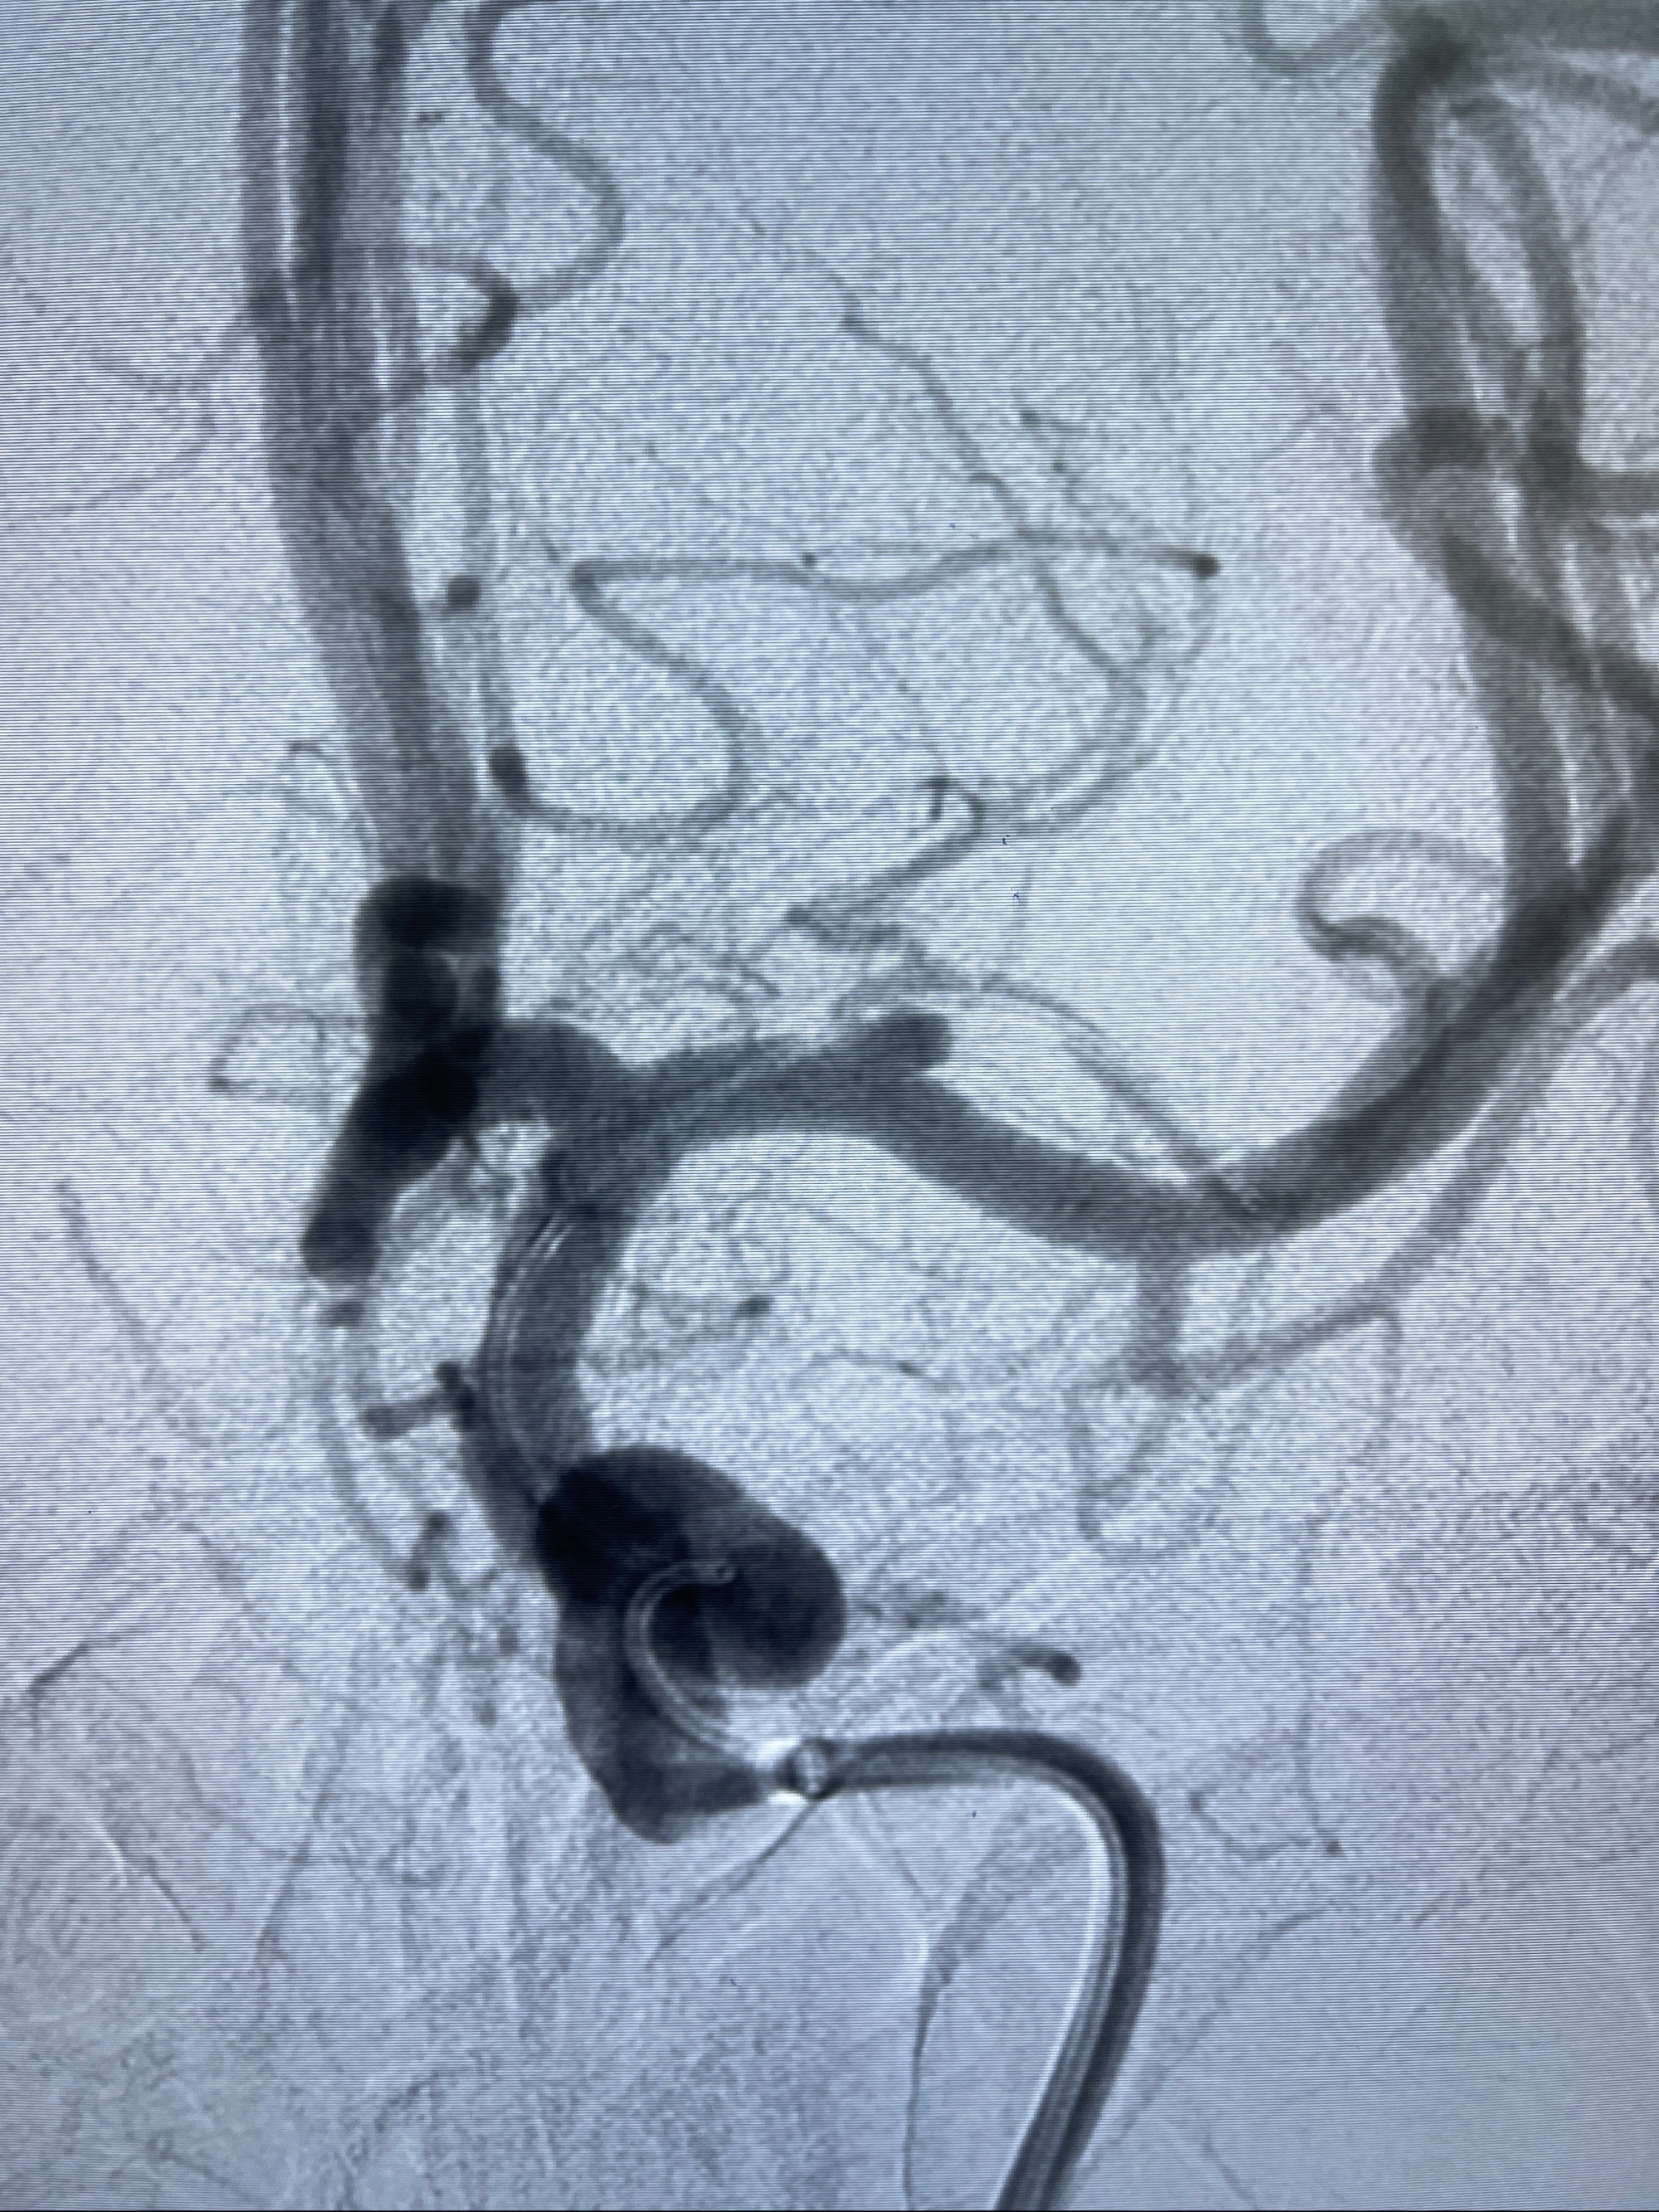

治疗策略:

1.左侧大脑中动脉动脉瘤,约2.6-2.8-3.4-2mm大小(瘤颈部、瘤体部、瘤高)

2.外科手术夹闭or介入支架辅助栓塞